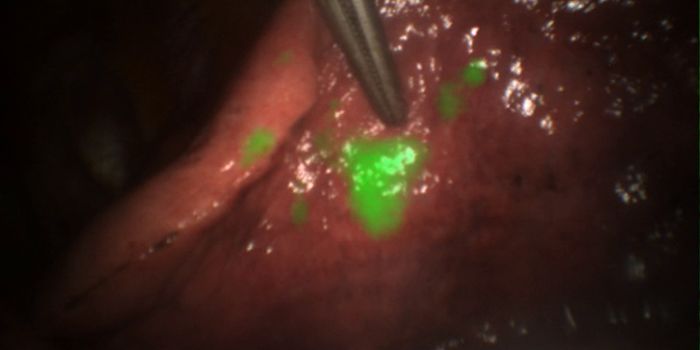

JUL 13, 2021Clinical & Molecular DXResearchers have developed the first diagnostic “pen” that acts as a guide for surgeons, helping them distin ...